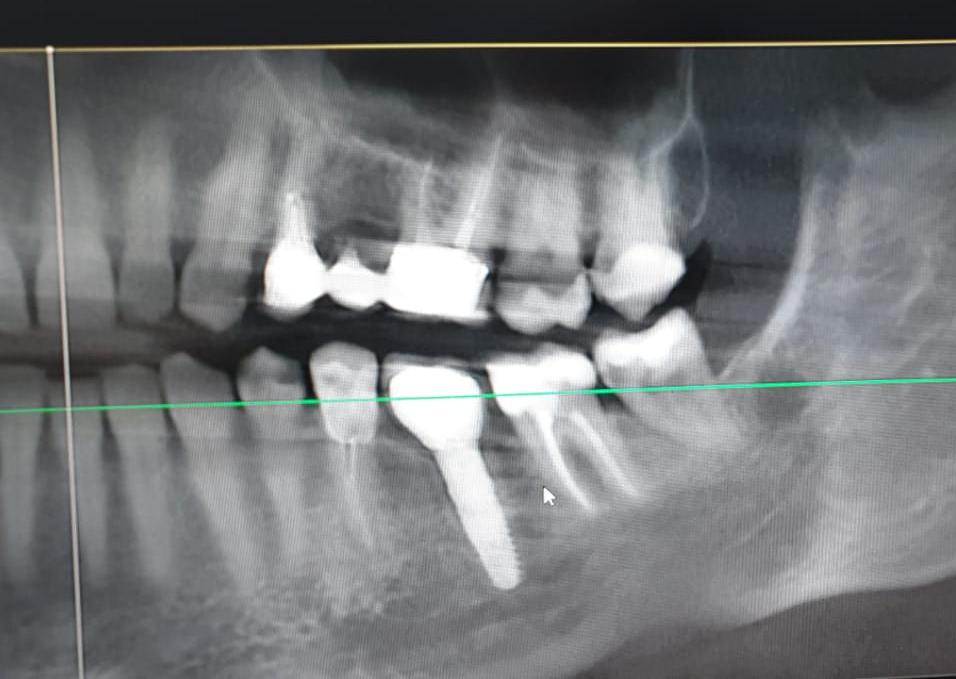

rivezico Опубликовано 30 июля, 2021 Поделиться Опубликовано 30 июля, 2021 Добрый день! Пациент около 10 лет назад ставил имплантат. Решили переделать коронку. У пациента было в плане из той клиники написано "имплантат impro". В итоге решили взять для имплантиума слепочный трансфер. В дентал гуру сказали, что они взаимозаменяемы. Но трансфер сел, а вот винт не прикручивается. Скинули прицел имплантата в дентал гуру, нам сказали, что это не impro... Пациент пытается выяснить в той клинике, но того доктора уже нет и непонятно, получится ли выяснить спасибо) Ссылка на комментарий

АнтонТЛТ Опубликовано 30 июля, 2021 Поделиться Опубликовано 30 июля, 2021 Xive это, только формирователь не от него 1 Ссылка на комментарий

АнтонТЛТ Опубликовано 31 июля, 2021 Поделиться Опубликовано 31 июля, 2021 1 час назад, Irouil сказал: Xive с конусом? И где полированная фаска? Без конуса, то что конусный фдм туда прикрутили, не значит, что сам интерфейс имплантата конусный) Фаска выше линии замера 2 Ссылка на комментарий

АнтонТЛТ Опубликовано 1 августа, 2021 Поделиться Опубликовано 1 августа, 2021 Абатмент xive)) 1 Ссылка на комментарий